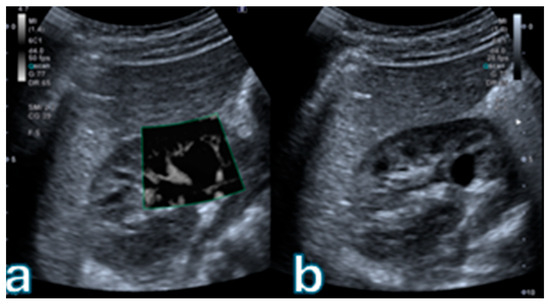

Figure 1

Background: Accurate characterization of complex renal cystic lesions is essential for individualized patient management, as enhancement patterns of septa and walls determine Bosniak classification, malignancy risk, and tailored follow-up strategies. While contrast-enhanced ultrasound (CEUS) is widely used to assess enhancement, Superb Microvascular Imaging (SMI) offers a non-contrast alternative that is capable of detecting slow-flow microvascular signals. This study aimed to evaluate the diagnostic concordance, accuracy, and reproducibility of SMI compared with CEUS in the Bosniak 2019 classification, and to explore its role in personalized imaging pathways for patients with contraindications to contrast media. Methods: Eighty patients (92 cystic renal lesions) who underwent both SMI and CEUS between January 2024 and July 2025 were retrospectively analyzed. Lesions were categorized using the Bosniak 2019 criteria. CEUS served as the reference standard. Concordance between modalities was evaluated using Cohen’s κ, and diagnostic accuracy was determined by ROC analysis. Inter- and intra-reader agreement were assessed with κ and intraclass correlation coefficients (ICC), respectively. Histopathologic confirmation was available for resected Bosniak III–IV lesions. Results: SMI showed excellent concordance with CEUS (κ = 0.84, 95% CI 0.76–0.91; overall agreement 83.7%). Concordance was perfect for Bosniak I–II, good for IIF (85%), and moderate for III (68%) and IV (64%) categories. Using CEUS as the reference, SMI achieved a sensitivity of 88.5%, specificity of 90.0%, and AUC of 0.94 for distinguishing low- from high-risk lesions. Inter-reader (κ = 0.83) and intra-reader (ICC = 0.91) agreements were excellent. Among 18 surgically resected Bosniak III–IV lesions, 14 (77.8%) were malignant; SMI correctly identified 12/14 malignant and 3/4 benign cases. Conclusions: SMI shows high diagnostic accuracy and reproducibility in the assessment of complex renal cystic lesions, with strong concordance to CEUS within the Bosniak 2019 system. By providing vascular characterization without contrast administration, SMI supports more personalized renal cyst management, enabling safer imaging for patients at risk from contrast agents and potentially reducing unnecessary interventions. Further multicenter validation is warranted to define its integration into precision-oriented multiparametric renal ultrasound protocols. Full article